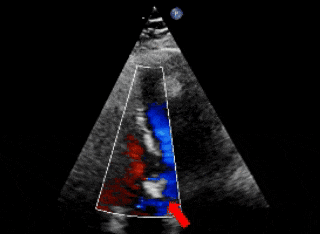

超声下可见右冠窦与右心房相通,主动脉短轴切面示类似膜周部室缺

保留导丝技术,展开封堵器左盘(左);超声下可见左盘面贴靠主动脉侧(右)

右盘面展开后,前推钢缆使其成型(左);超声下可见双盘面骑跨(右)